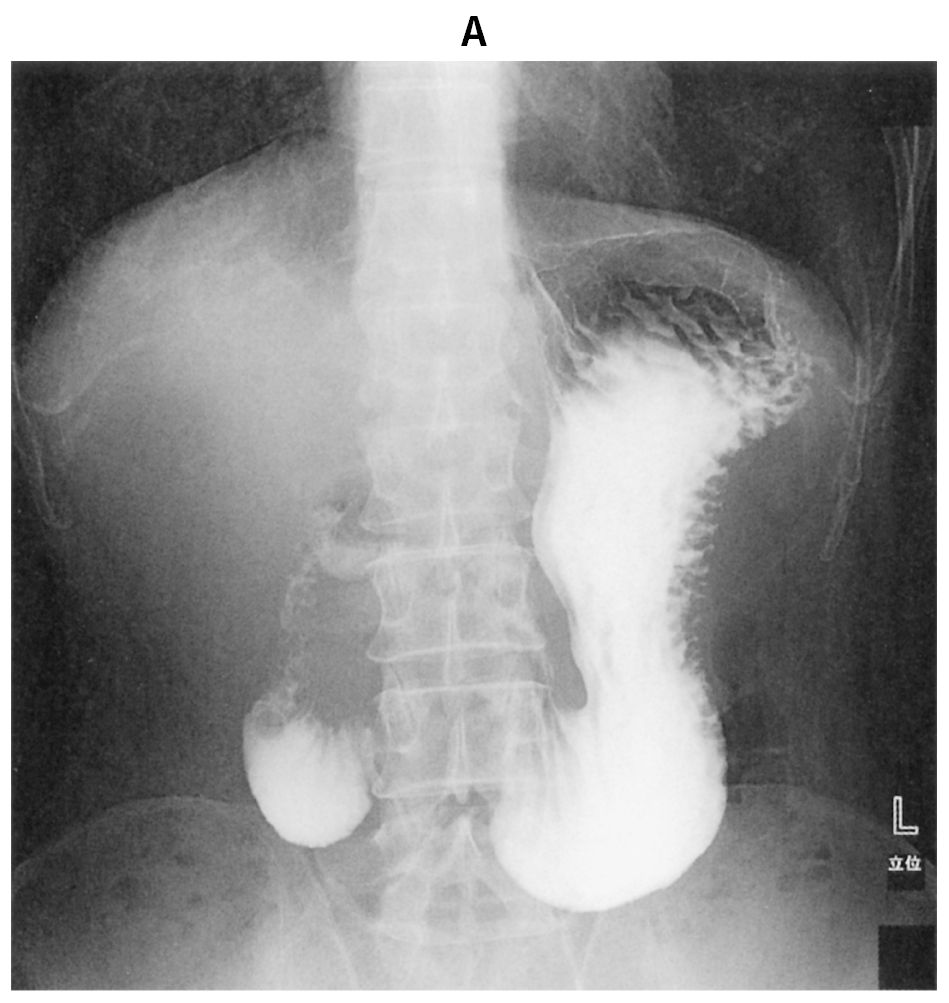

30歳の女性。嘔吐と体重減少を主訴に来院した。6か月前から仕事のストレスで食欲が落ち,体重が55kgから40kgまで減少した。その後,食後の悪心と嘔吐を繰り返すようになり,徐々に体重が減少するため受診した。上半身を前屈して食事をとると,食後の症状は軽減する。吐物に血液の混入は認めない。黒色便は認めない。意識は清明。身長160cm,体重35kg。体温36.5℃。脈拍72/分,整。血圧106/68mmHg。呼吸数20/分。SpO2 98%(room air)。眼瞼結膜は軽度貧血様であり,眼球結膜に異常は認めない。腹部は陥凹しているが,圧痛を認めない。血液所見:赤血球412万,Hb 10.2g/dL,Ht 38%,白血球5,600(好中球62%,好酸球3%,単球5%,リンパ球30%),血小板27万。血液生化学所見:総蛋白6.9g/dL,アルブミン3.3g/dL,総ビリルビン1.0mg/dL,直接ビリルビン0.4mg/dL,AST 17U/L,ALT 20U/L,尿素窒素28mg/dL,クレアチニン0.5mg/dL,CEA 2.5 ng/mL(基準5以下),CA19-9 17U/mL(基準37以下)。CRP 0.1mg/dL。水溶性造影剤による上部消化管造影像(A)(B)を下に示す。BAの20分後の像である。造影剤が十二指腸に停滞し,空腸への流出がみられなかった。